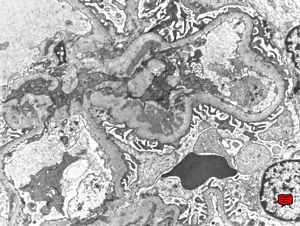

M,22y. | type II membranoproliferative glomerulonephritis